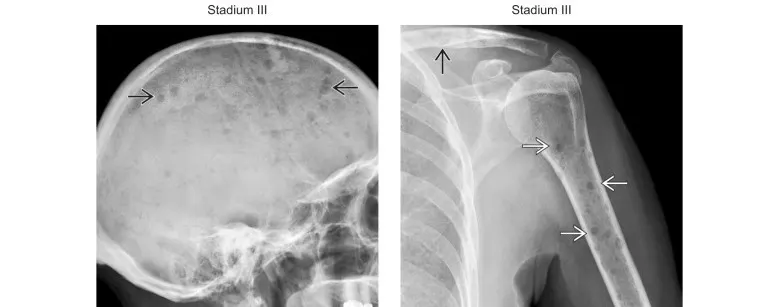

(Gauche) La radiographie sagittale du crâne montre de nombreux foyers lytiques infracentimétriques (→). (Droite) La radiographie frontale de l’épaule gauche chez le même patient montre de multiples foyers lytiques infracentimétriques dans l’humérus proximal (→) et la clavicule (↑). Plus de 20 foyers lytiques correspondent au stade III de la maladie.